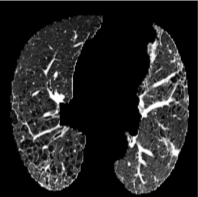

Based on Eqn. (2), we can identify the most influential cluster contributing to the final score for each individual by vectorizing the feature for each cluster. The heatmap in Supplementary Fig. 2 represents the contribution of the cluster to the final patient-level risk score on the FLD dataset, where the panels from left to right depict the vectors for patients arranged in decreasing order of value. The rationale behind each patient’s final prediction: the red cube highlights clusters contributing to high-risk scores, while blue indicates a lower risk. From this visualization, we can see that patients with different prediction results are highly disentangled, and the contributing patterns are clearly delineated for each patient. The most influential clusters across the dataset are determined by comparing the average values between the two classes with different predictions. The ranking of clusters by contribution to the ‘mortality in one year’ class on the FLD dataset is shown in Supplementary Fig. 3 and the most representative slice patterns are provided in Supplementary Fig. 4, which show that the model can identify common clusters within each class group, enabling us to pinpoint most significant features by visualizing the most frequently contributing clusters among patients.

Cluster 28